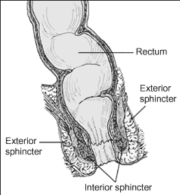

| 11:53, 21 בינואר 2024 | Anorectum.png (קובץ) |  |

179 קילו־בייטים | Motyk | 1 | |